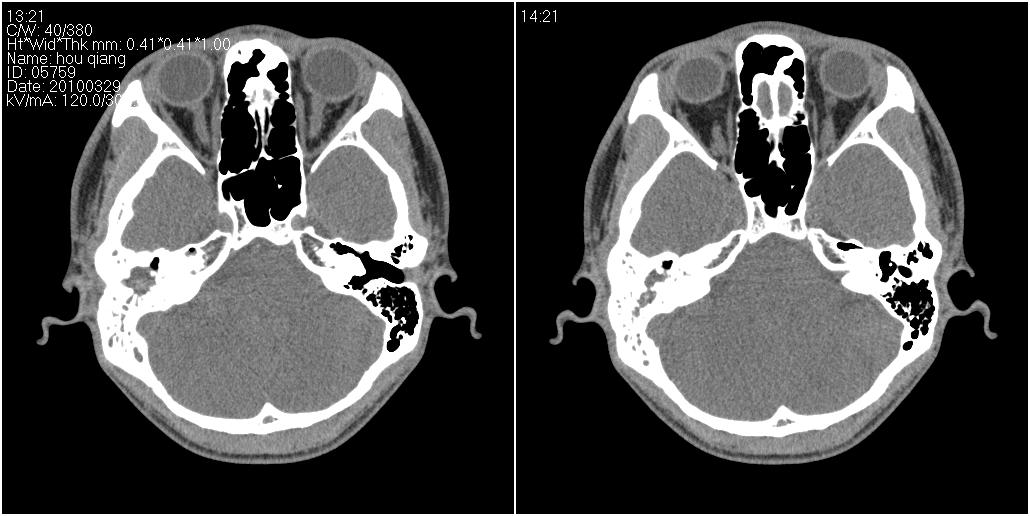

标题: CT25419:男性,18岁。右耳肿、痛5个多月。 [打印本页]

标题: CT25419:男性,18岁。右耳肿、痛5个多月。

1)右侧慢性中耳乳突炎并右侧中耳腔及外耳道肉芽肿或胆脂瘤形成。2)鼻咽腺样体肥大。

右侧中耳乳突炎累及外耳道,鼻咽腺样体肥大。